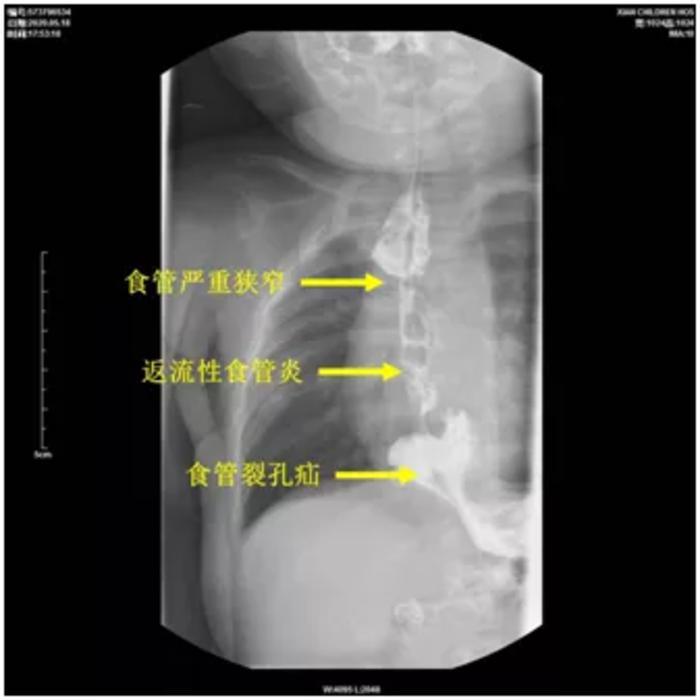

患儿小依依(化名)出生时即患有先天性食管闭锁与气管食管瘘疾病,虽然经过外科手术治疗,但术后吻合口出现严重食管狭窄。虽经多次内镜扩张治疗,但仍然反复再次发生食管狭窄,使小依依不能像其他孩子一样正常喂养,甚至吃奶喂水也会出现频繁呕吐、呛咳。经西安市儿童医院造影检查,发现小依依除了患有食管严重狭窄外,还患有食管裂孔疝(即部分胃通过食管周围的孔隙进入胸部)和严重的胃食管返流疾病,因患儿食管狭窄几乎完全堵塞,仅约1mm孔隙,病情严重。